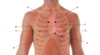

Label A-H

a. ) auscultation position for aortic valve

b. ) aortic valve

c. ) tricuspid valve

d. ) auscultation position for tricuspid valve

e. ) auscultation position for pulmonary valve

f. ) pulmonary valve

g. ) mitral valve

h. ) auscultation position for mitral valve

Ausculatation position for aortic valve is located at:

right sternal angle of 2nd intercostal space

auscultation position for tricuspid valve:

left sternal margin of 5th intercostal space

Auscultation position for pulmonary valve:

left sternal margin of 2nd intercostal space

Auscultation position for mitral valve:

mid clavicular of the left 5th intercostal space (hearing mitral valve at apex of heart)